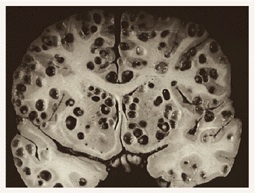

http://i.imgur.com/O4dlwUi.jpg

(管理人注:画像閲覧注意)

http://i.imgur.com/XM8HPbJ.jpg

蓮コラ並み

>>51>>52

オワリダナ

>>51-52

背筋ぞわっとした今までで最悪のグロ画像

多数の穴があいた脳みその画像ですよ。51と大して変わらないです。グロさは…まぁそれなりに…